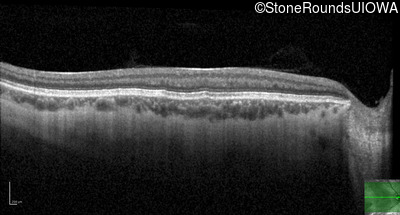

Optical Coherence Tomography - Right - 20/80 +2

Exemplar / OCT Stack

OCT Stack